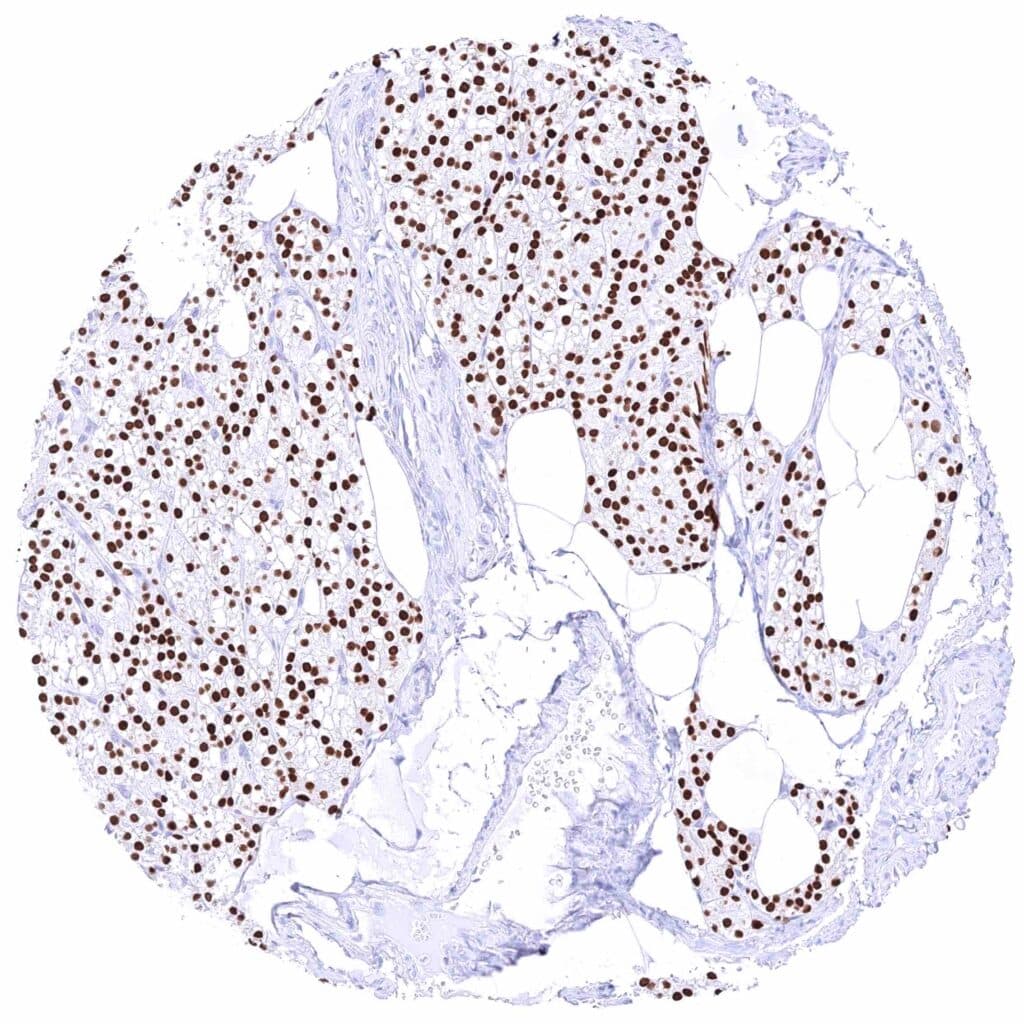

Parathyroid gland – Strong nuclear GATA3 positivity of all epithelial cells. .jpeg